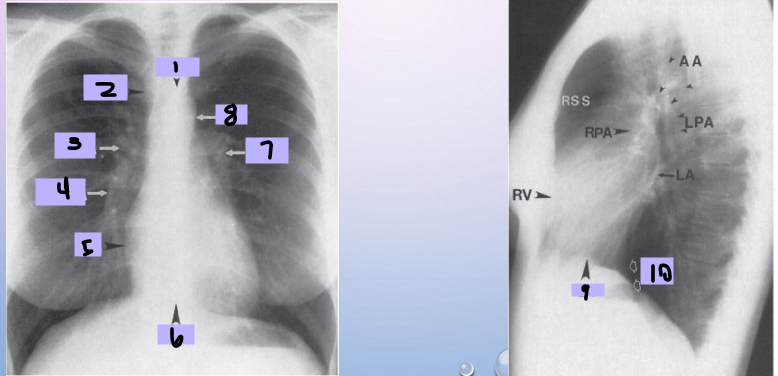

Aortic arch

#1

Superior vena cava

#2

Right pulmonary artery

#3

Right descending pulmonary artery

#4

Right atrium

#5

Right ventricle

#6

Left pulmonary artery

#7

Descending aorta

#8

Left ventricle

#9

Inferior vena cava

#10